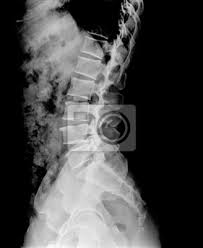

Coluna lombar - perfil em extensÃo mÁxima Paciente Em decúbito lateral ortostático PMS paralelo à LCELCM posicionar de modo que a coluna lombar fique sobre esta linha fazer a extensão ao máximo do paciente forçando ombros e quadris para trás os membros superiores na cabeça ou para atras. Rx de Coluna Inteira. RX Coluna Lombar APPerfilL5S1 Em breve você realizará o exame de RX que visa avaliar ossos e estruturas. Rx de coluna cervical dorsal e lombar para escoliose. Têm uma Smart Fit te esperando agora mesmo. O exame é contraindicado para gestantes salvo em situações nas quais absolutamente. Em casos de RX com contraste poderemos necessitar de punção venosa ou sondagem a depender da indicação e avaliação prévia pela equipe responsável. Não é possível identificar hérnias de disco com esse exame. RX COLUNA DORSO LOMBAR PARA ESCOLIOSE.

PREPARO Chegar 20 minutos antes do horário marcado. Rx da Coluna Lombar - APPERFIL. RX Coluna Lombar APPerfilL5S1 Em breve você realizará o exame de RX que visa avaliar ossos e estruturas. RX DE COLUNA LOMBAR FRENTE E PERFIL PERFIL DO SACRO PARA QUE O EXAME SEJA REALIZADO O PACIENTE DEVE. I - Informações sobre o exame - Trata-se de exame de raios X da coluna lombossacra em flexão e extensão. Obviamente isso não significa que outras causas potenciais de dor lombar não justifiquem imagens médicas imediatamente ou posteriormente. Não perca a chance de treinar na maior rede de academias da América Latina.